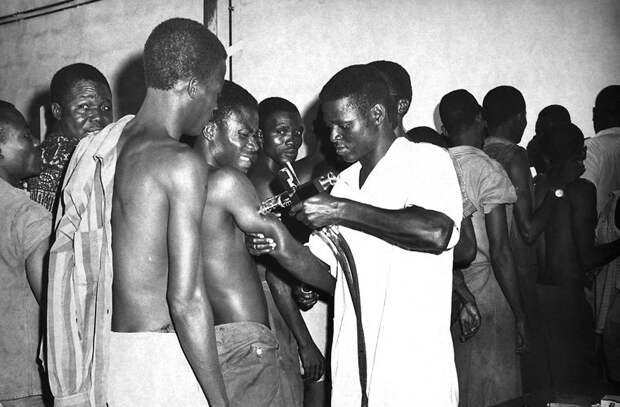

Прививка от желтой лихорадки

Будучи практикантом в одной из пенсильванских больниц и решив опровергнуть версии о заразности болезни, Фирф был крайне изобретателен в доказательных методах. Закапывая рвотные массы, полученные от больных, себе в глаза, поливая ими разрезы, сделанные на теле и даже выпивая их в большом количестве, Фирф так и не заразился. Однако он глубоко заблуждался в своей теории. Все дело в том, что желтая лихорадка передается при попадании в кровоток, обычно при укусах комаров. К сожалению, эта информация впервые появилась спустя 60 лет после смерти Стаббинса Фирфа — в работах кубинского врача Карлоса Финлея, а экспериментально была подтверждена лишь в 1900 году.